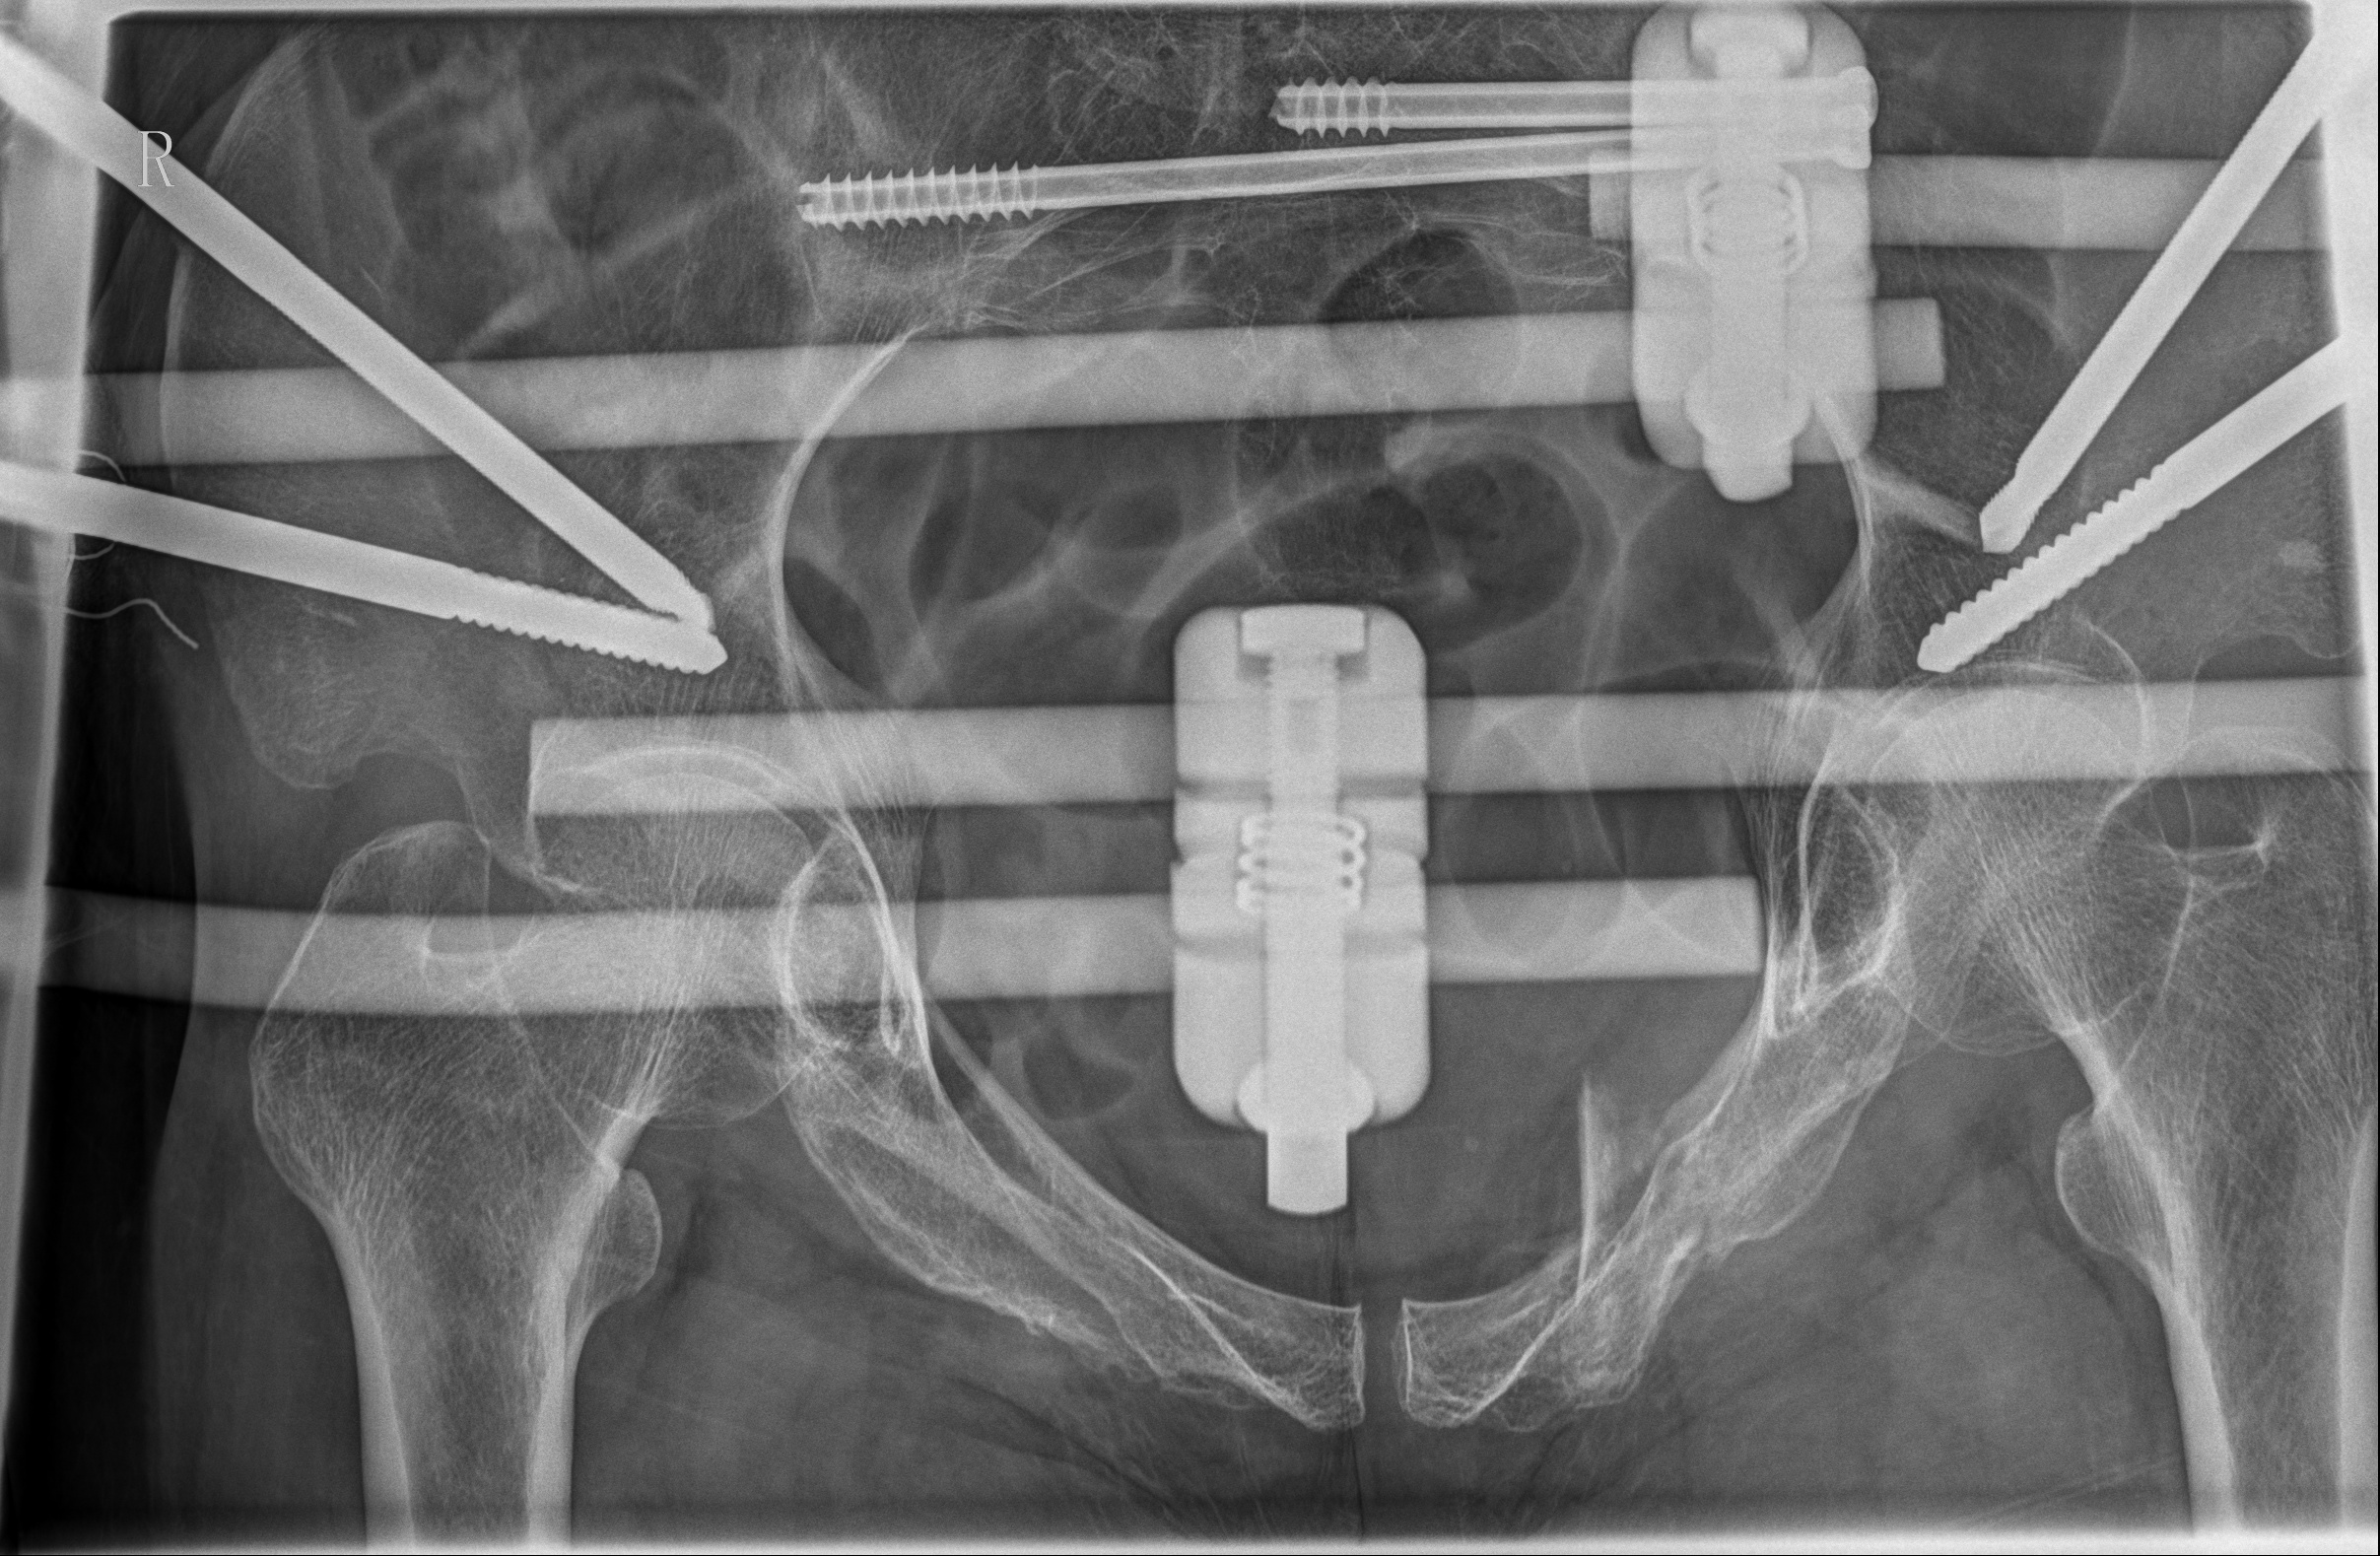

术后骨盆CT片

在手术过程中,骨科手术机器人展现了卓越的性能。通过精确的术前规划和实时的术中导航,医生仅通过几个微小的切口(每个仅1cm长),便成功地置入了2枚骶髂螺钉和4枚骨盆外固定Schanz钉。在骨科手术机器人的辅助下,此次手术时间较传统手术明显缩短,术中失血量仅约20ml,手术创伤小,大大降低了手术风险。值得注意的是,此次手术采用新型的骨盆支架外固定术,该技术可将Schanz钉完全置入髂骨内外板之间并打入髋臼顶相对致密且丰厚的骨质内,使骨盆骨折得到了有效固定,且该技术具有基于触诊、不依赖透视、置钉精准且深入的优势。得益于骨科手术机器人微创手术治疗,该患者在术后3天即顺利出院,体现了现代快速康复理念。骨科手术机器人技术的顺利开展,标志着金瓶梅电影 在数字智能治疗复杂骨盆骨折疾病方面迈入精准微创新高度。